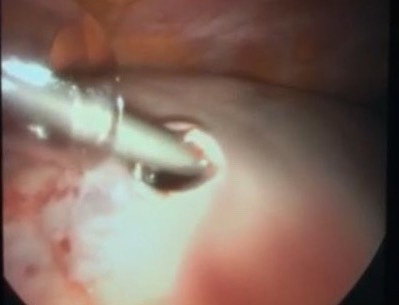

An adnexal mass (mass of the ovary, fallopian tube, or surrounding connective tissues) is a common gynecologic problem. In the United States, it is estimated that there is a 5 to 10% lifetime risk for women undergoing surgery for a suspected ovarian neoplasm. Adnexal masses may be found in females of all ages, from fetuses to older adults, and there are a wide variety of types of masses.  Today, the surgical treatment has become more conservative and less invasive; hence, a laparoscopic approach in the presence of benign cysts has become a golden standard. In the past, patients with previous abdominal surgery were discouraged from undergoing laparoscopic surgery because of its increased risk of bowel injury caused by needle and trocar insertion. Complications occur two times more frequently in patients with previous laparotomy in a study of long series. The potential risk for injury of organs adherent to the abdominal wall during veress needle or trocar insertion as well as the necessity for adhesiolysis and its attendant complications are the two major specific problems constraining surgeons from performing laparoscopic cystectomy/ oophorectomy for patients with previous abdominal surgery. Herein, we report a case of a 32-year-old woman P4 + 2 with history of previous four cesarean section and a following laparotomy for interval sterilization presented to our clinic with abdominal mass, discovered by ultrasound scan, managed by a laparoscopic approach.